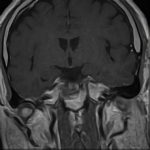

218

'21年9月

80代

左後頭頂葉腫瘤

頭蓋内腫瘍摘出術

No.’21_62 手術前1

No.’21_62 手術前2